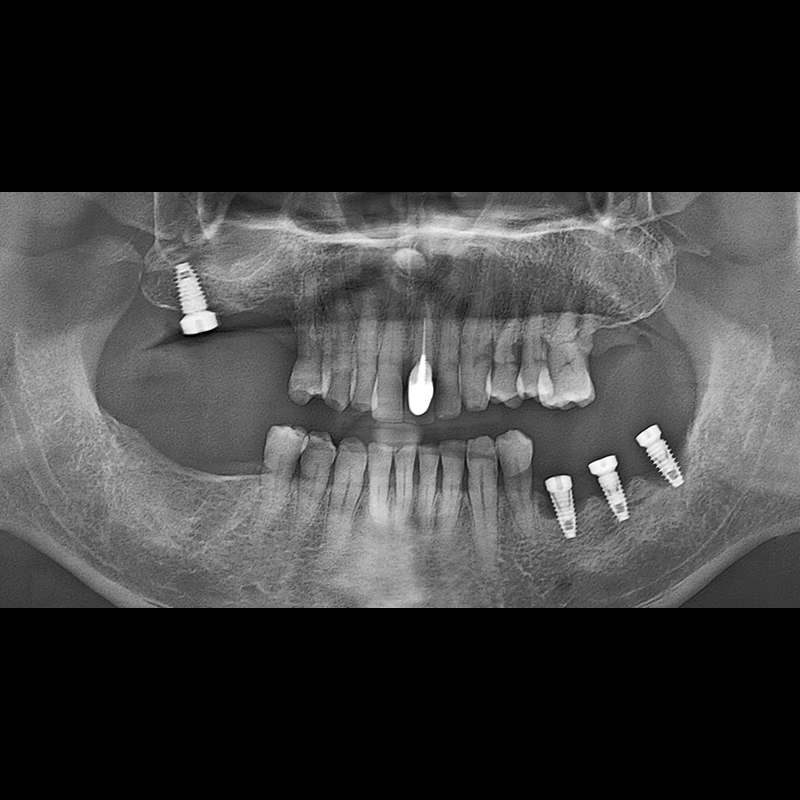

BEFORE AFTER

种植牙前后的照片 2025.05.30

在缺失的牙齿部分和难以挽救的牙齿位置植入了种植牙。